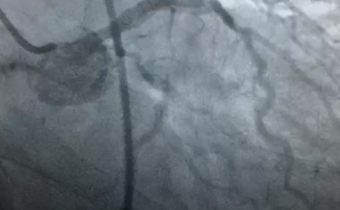

Caso clínico: Arteriopatía coronaria